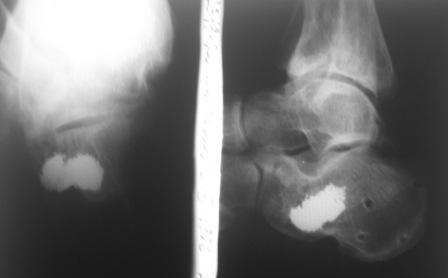

Приветствую,коллеги!Извините,но немного непонятно , как можно советовать, основываясь на только одной проекции. Извините, но необходимы, как минимум, аксильная (Харриса) и косая (Бродена)проекции . Это даёт неоходимый минимум информации о степени разрушения подтаранного сустава. Хорошо бы так же иметь КТ и фото мягких тканей(внешний вид пятки). После этого стоит говорить о тактике лечения

Уважаемый Дмитрий! Абсолютно с Вами согласен, но думаю, что это уже частности необходимые для предоперационного планирования и зависят от мощности лечебного учереждения, чем и будет заниматься доктор непосредственно сам. Вопрос же принципиально заключается как оперировать? И мне кажется, что даже по этому малоинформативному снимку Вы представляете степень разрушения кости.